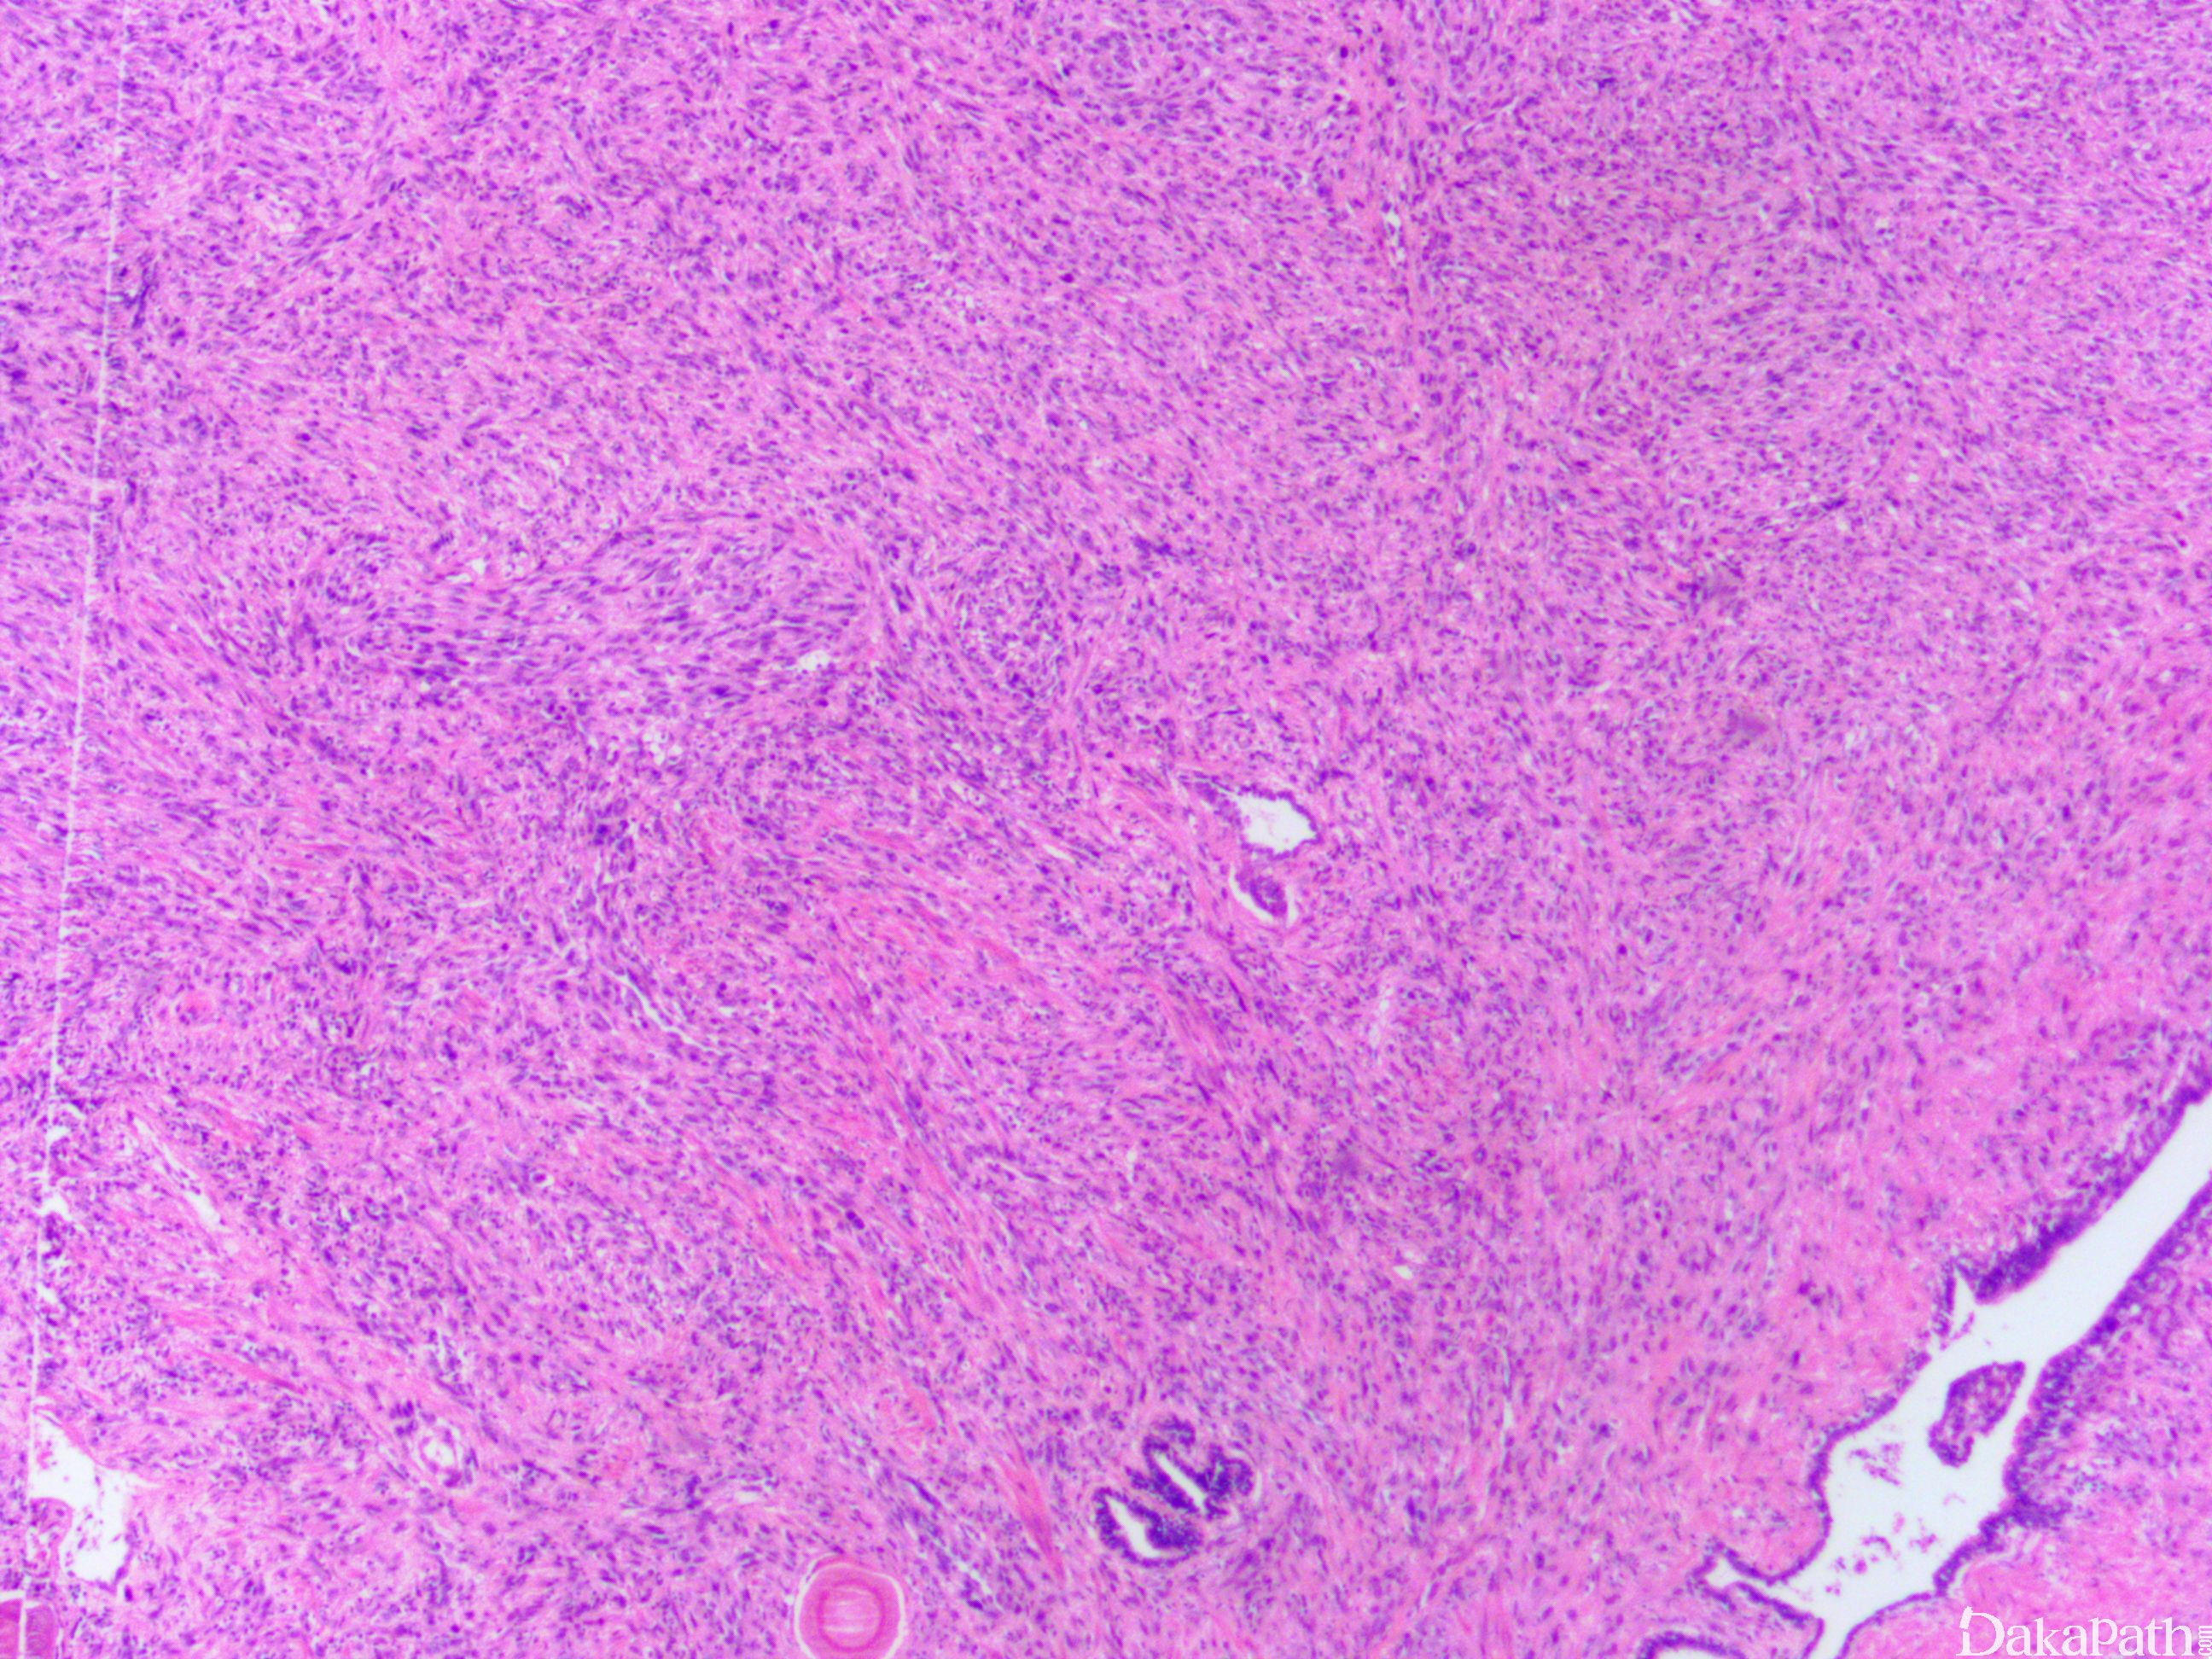

前列腺腺泡性腺癌,肉瘤样型

Prostate Acinar Adenocarcinoma,Sarcomatoid Variant

具有上皮样与肉瘤样双向分化成分。

- 上皮成分通常表现为 Gleason 高级别的腺泡性腺癌;

- 肉瘤样成分可包括异源性的骨肉瘤、软骨肉瘤、横纹肌肉瘤、脂肪肉瘤、血管肉瘤及其它多种异源成分。

上皮成分 CK、PSA、PAP 阳性,肉瘤样成分 CK 表达减少,或表达相应的间叶组织抗原。